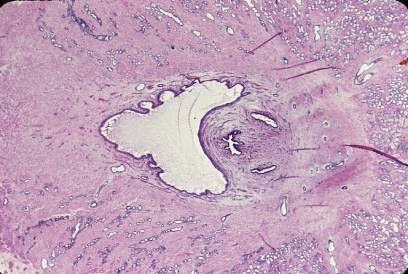

サル、SUSA液で固定、セロイディン包埋、H-E染色、x 10.

これは精丘を通る前立腺の水平断面であり、画面の左が前、右が後ろである。-

尿道は前立腺の前方部を上から下に向かって貫通しており(尿道前立腺部)、--

その後壁の中央部は尿道に向かって小丘状に高まっている。これが精丘であ---

る。精丘の基部の上下に見られる細長い管が射精管、精丘の中央部の星形の---

腔所は前立腺小室である。前立腺小室は発生早期のミュラー管の名残である。

射精管はその名に反して、この図に見られるように、その壁に筋層を持たず、

精液を射出する機能を持たない。-------------------------------------------------------

Monkey, fixation with SUSA-fluid, embedding with celloidin,H-E stain, x 10.

This is a horizontal section of the prostata through the colliculus seminalis.--

The urethra pierces the anterior portion of the prostata from top to bottom--

and

at its middle portion the posterior wall protrudes into the lumen as the--

colliculus seminalis. From its top a small outpocketing, utriculus prostaticus,

appears backward. This is the rudiment of Mullerian canal. At lower end of--

the colliculus seminalis a pair of ejaculatory ducts opens into the urethra.----

Though of the name, ejaculatory duct has no musculature in its wall, so that

it has no ejaculatory function. In this figure right to the utriculus prostaticus

a pair of ejaculatory ducts is seen.-------------------------------------------------------